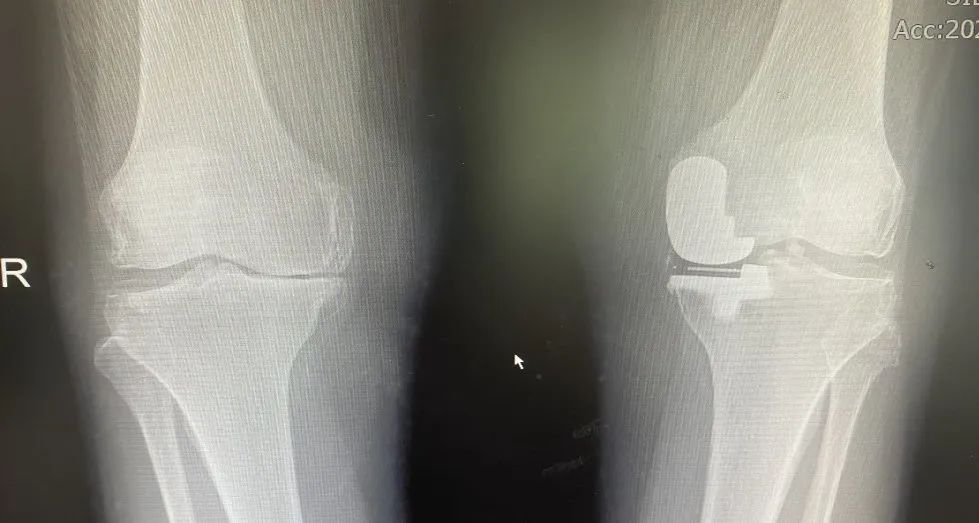

▲术前(上图)术后(下图)影像资料

后经人介绍,刘奶奶在我院经相关检查后,行左膝单髁关节置换术,手术非常顺利,术后恢复良好,左膝关节无疼痛,活动自如。近两月,患者右膝关节的旧疾疼痛加重,复查发现这又是右膝内翻畸形带来的“烦恼”。于是便在我院再行右膝单髁关节置换术。现术后双膝关节活动自如,行走无碍。困扰了刘奶奶20多年的“老毛病”至此终于告一段落!